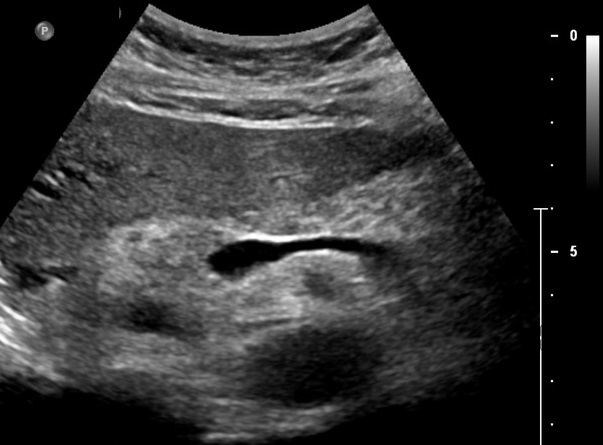

Aspect radiologique TDM d.'

une adenocarcinoma de la tete du pancreas , c'est un

masse tissulaire hypodensite a bord tres nette situe

a la tete du pancreas ( fleche rouge ) . Par

l'obtacle de la tumefaction le signe indirect

se presenter c'est image de dilatation en amont du

canal pancreatique principale ( fleche jaune ) |